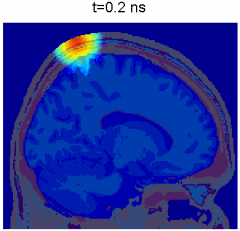

Monte Carlo simulation of photon propagation inside non-uniform tissue structures, has important applications in medical imaging, such as brain scans, but it is extremely computationally intensive.

Simulation of photon transport inside human brain - animation courtesy the researchers

To compensate for this, Qianqian Fang, formerly a biomedical imaging researcher at the Massachusetts General Hospital, since September 2015 an Assistant Professor of Bioengineering at Northeastern University, developed Monte Carlo eXtreme (MCX for short), one of the first massively parallel photon migration simulation frameworks. Now widely used across the bio-photonics research communities, MCX has clocked up over 12000 cumulative downloads, with over 30, 000 users to-date worldwide.

Monte Carlo eXtreme, or MCX, is a Monte Carlo simulation software for time-resolved photon transport in 3D turbid media. It uses GPU based on massively parallel computing techniques and is extremely fast compared to the traditional single-threaded CPU-based simulations. Using an NVIDIA GTX 980 graphics card, the acceleration is about 300x-400x compared to a single thread on an Intel Core i7 4770k.